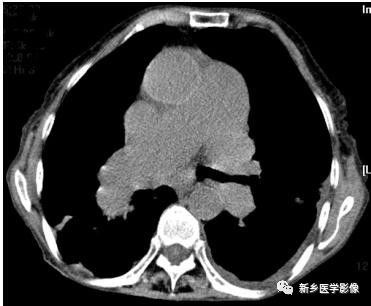

肺水肿CT图像